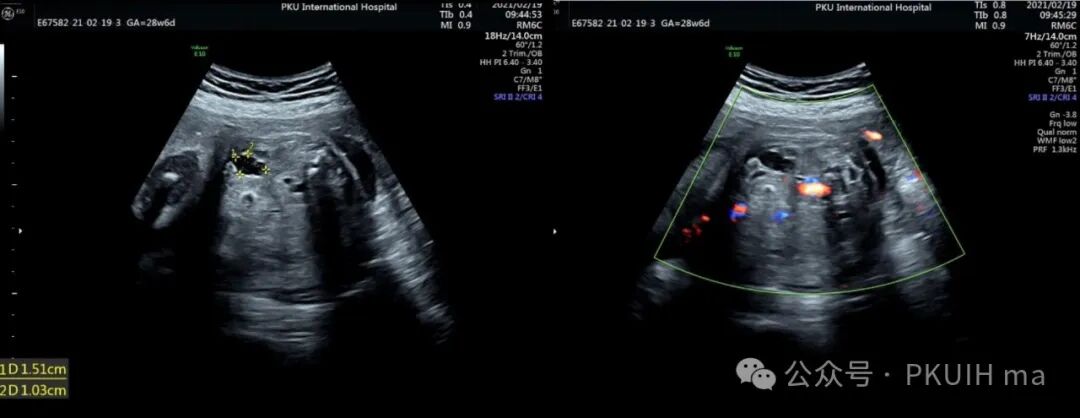

上图是一个28周发现的腹腔囊肿,在随后的观察及出生后随访中均无明显变化,生后超声提示位于肠壁外侧,初步考虑肠重复畸形或肠系膜囊肿。从产前超声图像看内壁不光滑,囊壁回声增强,可能是小肠的肠重复囊肿